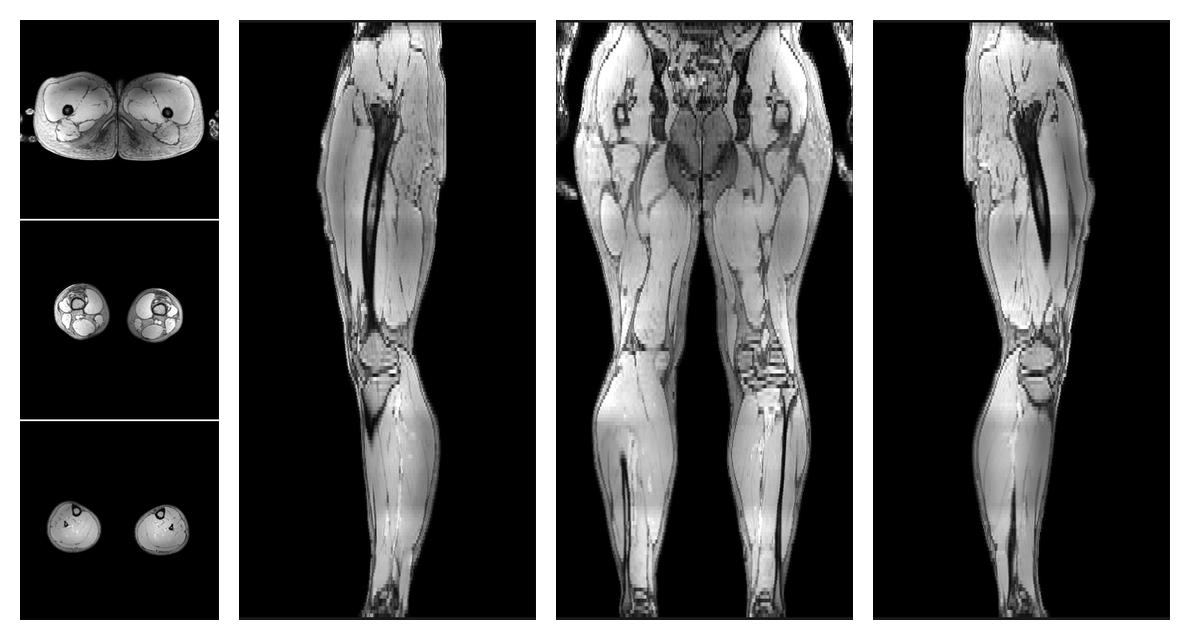

Water only T2 mapping

Multi echo spin echo T2 relaxation time mapping with EPG reconstruction, for information look here».

• Water only signal

The water part of the acquired multi-echo spin echo data.

• Water only T2 relaxation time

The water only T2 relaxation time of the lower extremity obtained from multi echo spin echo t2 mapping with EPG based reconstruction.